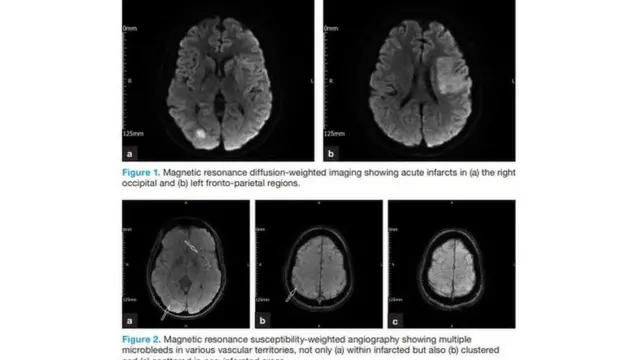

ډاکټرانو د کمپیوټري انځورونو یا سیټي سکن په مرسته وموندله چې د عمر په مغزو کې د وچې شوې یا غوټه شوې وینې کوچنۍ ذرې پرتې دي.

دوی په دې باور دي چې دا وینه د عمر په بدن کې د کورونا وېروس د شتون له کبله وچه شوې ده.

د وینې همدا ټوټې د دې لامل شوې چې د عمر پر مغزو یا اعصابو حمله راغله او نوموړی تر روغتونه ورسېد.

کمپیوټري انځورونو د عمر په مغزو کې ځینې داسې غیر عادي ځانګړتیاوې ښکاره کړې چې د ده د عمر ناروغانو کې نه موندل کېږي.